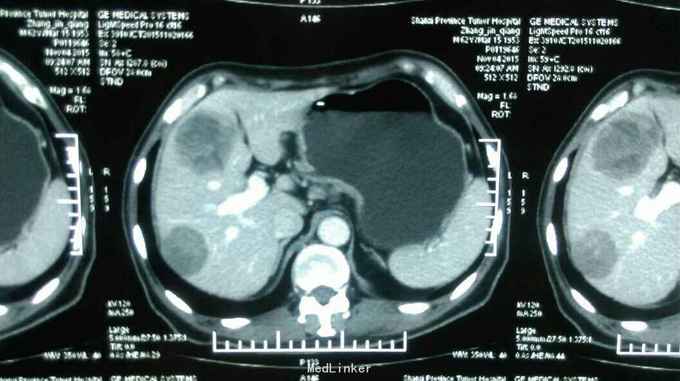

患者:男,62岁,主 诉:残胃癌多发转移化疗后,恶心呕吐5月余。 现病史:患者于2014年9月份自觉进食后上腹部饱胀感,就诊于忻州市人民医院,胃镜提示:胃大部切除术后,吻合口大弯侧粘膜隆起,充血,水肿,伴糜烂,质 脆,易出血,于2014年9月23日就诊于中国医学科学院肿瘤医院,诊断残胃癌,中分化腺癌,全腹部示CT提示:胃远端呈术后改变,吻合口扩张不良,吻合口壁厚,吻合口周围、胃左区新发现多发不均匀结节,大者短径约1.6cm;腹腔肠系膜根部、腹膜后多个小淋巴结;肝脏新出现多发结节,大者直径约1.5cm,考虑转移,盆腔少量积液。于2014年11月15日行XELOX方案化疗一周期,具体用药:奥沙利铂150mg,d1希罗达1500mg早 2000mg晚d1-d10,14天重复一次。后于忻州市人民医院2014年11月至2015年01月给予XELOX 方案化疗全身化疗5周期,化疗第二周期后,患者上腹部饱胀感减轻。于2015年3月12日就诊山西省肿瘤医院,全腹部CT提示胃腔缩小,残胃壁增厚,最后处约1.9cm,,残胃下方系膜内一枚囊性结节,大小约2.9X2.3cm,转移不除外:肝脏S8段一枚低密度灶,大小约为0.6X0.4cm;右肺中叶结节,大小约为1.6X1.4cm,肝脏S8段动脉期环形强化结节,考虑转移,右肺中叶炎性病变,继续给予行XELOX方案化疗2周期(奥沙利铂200mg,卡培他滨1.5g/次,2次/日,共14天)。因骨髓抑制明显,于2015年5月4日入该院后给予卡培他滨化疗一周期(卡培他滨2g/次,2次/日,共计14天)。2015年6月10日入该院复查CT提示肝内多发低密度影,部分新增,右肺中叶局限性肺不张,纵膈内多发小淋巴结,给予更换TP方案化疗一周期(多西他赛120mg,顺铂90mg),治疗结束于6月25日出院。出院后患者间断出现恶心、呕吐,于7月13日入该院复查胸腹部CT:残胃壁局部略变薄;头颅核磁未见异常。患者体质较差,不能耐受化疗,于7月21日始口服阿帕替尼250mg/日治疗。后患者间断出现恶心、呕吐,呕吐物为胃内容物,8月底患者停服阿帕替尼。9月8日入该院复查提示:肝脏多大转移增大,患者恶心、呕吐明显,予以留置鼻饲营养管,行EOF化疗一周期,共计用药:奥沙利铂150mg,表柔比星50mg,氟尿嘧啶3.0g,化疗所致骨髓抑制Ⅱ度。2015-11-02再次入住山西省肿瘤医院给予康莱特静点等对症治疗9天。目前患者每日鼻饲饮食后呕吐7-8次,每次呕吐量约40-50ml左右,全身疲软,精神食欲差,睡眠尚可,大便3-4日一次,较干结,小便基本正常,近3月体重下降约5kg。 既往史:既往患者高血压病史15年余,最高血压达180/100mmHg,平素口服尼福达片1片/日降压治疗,血压控制尚可;2型糖尿病10年余,曾皮下注射诺和灵30R控制血糖,近1月因进食量减少,已停用胰岛素治疗;40年前因“十二指肠穿孔”行胃大部除术;5年前山西医科大学第二医院确诊右半结肠癌行右半结肠切除术;10年前曾行阑尾切除术

诊断: 中医诊断: 胃癌 痰气交阻 西医诊断:残胃癌 中分化腺癌 浸润型 Lauren分型:肠型 肝转移 胃周 腹腔淋巴结转移 多疗程化疗后 空肠营养管植入术后: 呕吐原因待查 中度贫血 右半结肠癌(术后、化疗后) 2型糖尿病 治疗:入院给予查腹部立位片未见液气平面,给予止吐,输血纠正贫血,营养支持,中医中药扶助正气治疗,行动脉介入化疗药灌注(奥沙利铂150mg+氟尿密啶0.75g),肝转移灶(吡柔比星20mg+碘化油6ml)栓塞治疗。